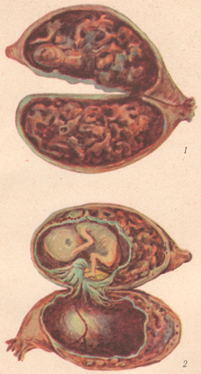

Медицина и диагностика: Инвазивный пузырный занос на УЗИ

Раздел: Альбом идей